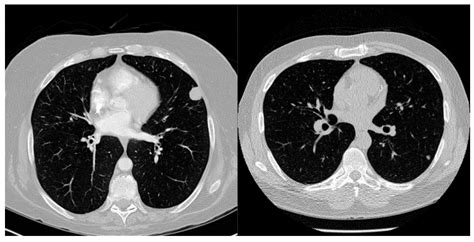

A Ground Glass Nodule is a type of lung nodule that appears as a hazy, increased opacity on a CT scan, without obscuring the underlying bronchial structures or vessels. This distinctive appearance sets GGNs apart from solid nodules, which completely obscure the underlying lung tissue. GGNs can be further classified based on their size and attenuation characteristics, which help in determining their potential malignancy.

• CT Scan: High-resolution CT scans are the primary imaging tool used to detect and characterize GGNs. These scans provide detailed images of the lung tissue, allowing radiologists to assess the size, shape, and attenuation of the nodule.

A 55-year-old male smoker with a 30-pack-year history of smoking presents with an incidental finding of a 10 mm GGN on a routine chest CT scan. The nodule is pure ground-glass in appearance with no solid components. The patient is asymptomatic and has no other significant medical history.

Initial CT Scan 10 mm pure ground-glass nodule